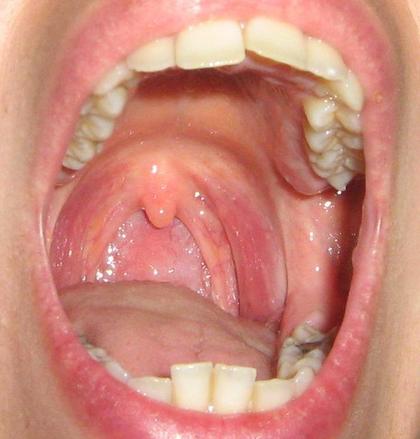

因炎症而红肿的咽部(图片来源:en.wikipedia.org)

慢性咽炎的症状局限于咽部,极少出现全身性不适。患者老觉得自己嗓子里有异物,疼痛或者发痒,早晨起来时可出现频繁的刺激性咳嗽,不过,不会吐痰,或者仅仅咳出颗粒状的分泌物。